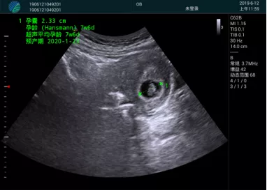

病例一:

清晰顯示孕囊,通過軟件包計(jì)算孕齡7w+6d

M20實(shí)時(shí)引導(dǎo),術(shù)中清晰顯示孕囊被破壞和抽吸針的過程,清晰顯示吸引針

抽吸結(jié)束后縱切子宮,孕囊已被完全抽吸,未見明顯殘留

橫切子宮,發(fā)現(xiàn)右側(cè)宮腔靠近宮角處有少許脫模樣殘留

M20引導(dǎo)下,抽吸針找到右側(cè)宮角處再次清掃

二次抽吸后再次進(jìn)行超聲檢查,宮腔未見殘留,宮腔線清晰顯示

超聲引導(dǎo)下可視化人流是技術(shù)安全性的保障,一般對(duì)人流術(shù)設(shè)備預(yù)算不高,M20具備婦產(chǎn)科軟件包,且穿透力圖像質(zhì)量好,既滿足人流引導(dǎo)需要,也可用于床旁超聲的需求。